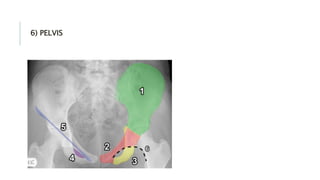

6) PELVIS